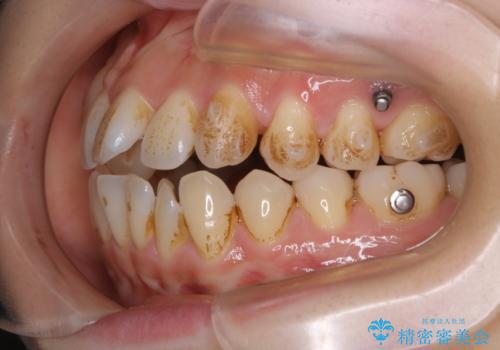

- インビザラインで矯正中に着色や歯石がついてしまったためクリーニングをしたいとのことで来院されました。

PMTC60分コースを行いました。

コーヒーによる頑固な着色や磨き残しによる歯石が多く付着していました。マウスピースをつけたままコーヒーを飲むこともあるそう。その場合は、なるべくはやくに歯磨きをしてマウスピースもしっかりと洗いましょう。